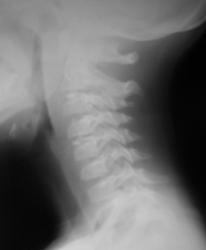

Ребенок 6 лет. Жалобы на выраженные боли в шейном отделе позвоночника. Со слов матери, боли в шее беспокоили длительное время. 2 недели отмечалась незначительная травма - девочка резко повернула голову в сторону, боли в шее услились. В настоящий момент  отмечаются выраженные боли в шее, резкое ограничение движений, повышение температуры тела, воспалительные изменения в анализах, (возможно, связанные с пиелонефритом, который также имеет место). Поступала с направительным диагнозом "ротационный подвывих атланта", однако данные рентгенографии заставили расширить круг диагностического поиска.Родовую травму мать отрицает. Хотелось бы узнать мнение уважаемых коллег.

Уважаемая коллега! С точки зрения классической рентгенологии (с учётом качества представленных снимков) могу высказать следующее:

- определяется выраженный антелистез тела С5;

- двуконтурность тел С3 и С5 может свидетельствовать о нарушении целостности костной ткани указанных тел позвонков;

- безусловно, межпозвонковые диски "поехали".

Вижу ещё раздвоенный axis.

Аксис не раздвоен, это нормальная картина для шести лет, просто верхушка зуба еще хрящевая.

Спасибо. Буду знать. По заданной теме: не хотелось бы быть освистанным, но смею предположить ювенильный ревматоидный артрит.

Случай помню. Закончилось все на удивление просто - после недели вытяжения петлей Глиссона боли ушли, движения в ШОП восстановились в полном объёме. Рентгенологические данные расценили как врожденную аномалию развития. Воспалительные изменения в анализах - как проявления пиелонефрита. В любом случае, из нашего поля зрения ребёнок ушел к нефрологам.